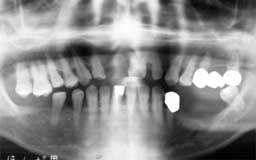

Iさん 初診時 54歳 女性

全体に歯周疾患による歯槽骨破壊が1/2以上進行し、他院で「全部抜いて総入れ歯」と言わ れたそうですが、歯牙保存を希望して来院されました

Iさん 14年後 68歳

歯周疾患抑制と動揺歯固定のため、全歯の抜髄と毎月の歯石除去を継続して行いました。 最終的に2本の歯を失いましたが、機能的には咬合関係を十分保持しています